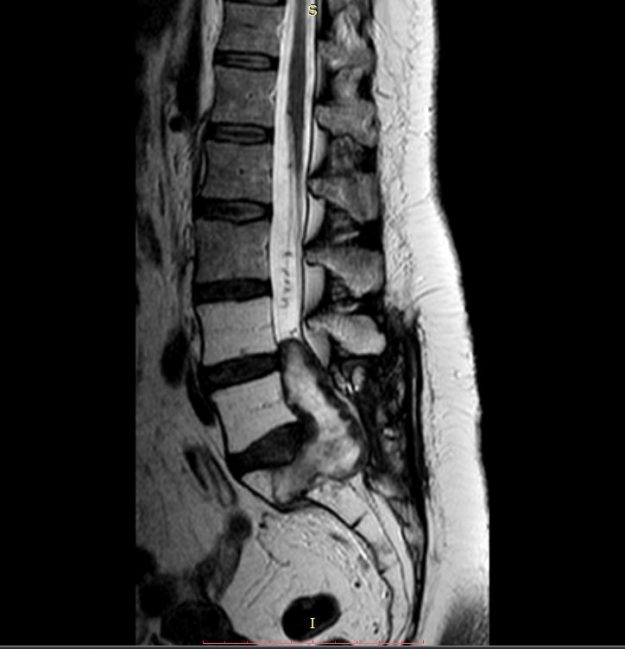

Νεαρή ασθενής 17 ετών με εκτεταμένη συριγγομυελία από την αυχενοπρομηκική συμβολή έως το τελικό τμήμα του νωτιαίου μυελού, λόγω συνδρόμου Chiari. Κλινικά αιμωδίες (μουδιάσματα) άνω άκρων, ζάλη. Αφού ο εργαστηριακός έλεγχος απέκλεισε συνοδά προβλήματα (πχ καθηλωμένο τελικό νημάτιο κ.α.) αποφασίστηκε η επέμβαση αποσυμφόρησης του οπισθίου κρανιακού βόθρου με ανάδυση των αμυγδαλών της παρεγκεφαλίδας και μηνιγγοπλαστική.…